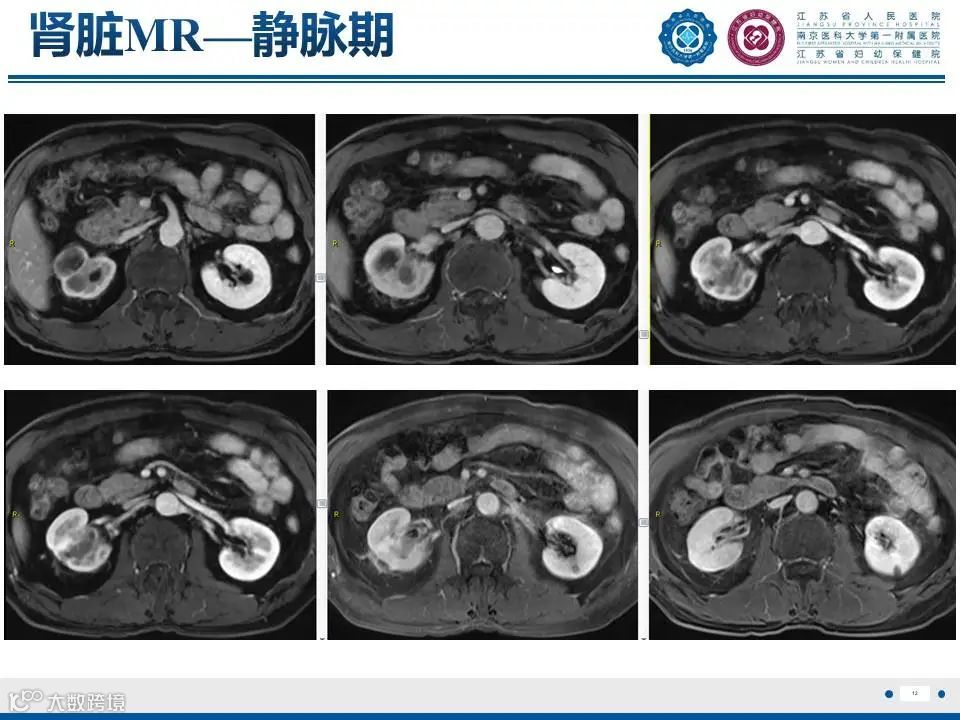

肾实质肾盂尿路上皮癌——水泄不通 II

肾实质肾盂尿路上皮癌——水泄不通 II 鼎湖影像